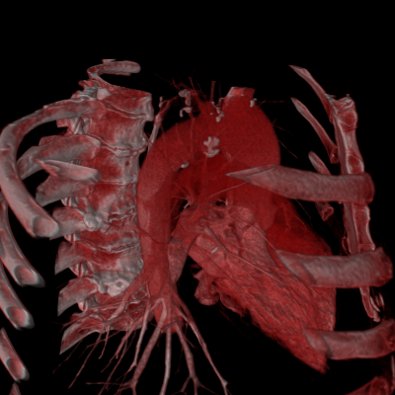

| Volume Data using 2D Texture | Volume Data using 3D Texture |

The 3D-Texture Visualization is very similiar to the 2D-Texture Visualization, but usually with a usually improved rendering quality. Since not all graphic cards support 3D-textures (yet), both visualization features have been implemented. If the "View 3d" shows only a "white box" instead of the loaded data, your graphic card does not support 3D-Textures.